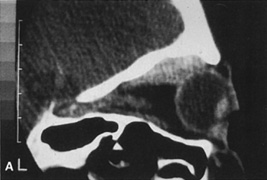

Valuable information about the nature and extent of an orbital pathologic process is provided by imaging studies such as computed tomography (CT) scan, magnetic resonance imaging (MRI), and orbital echography. Better spatial resolution, ready accessibility, and lower cost make CT the preferred choice for orbital imaging in most cases. Orbital fat provides a natural contrast between most adjacent orbital structures on CT scanning, and orbital bones are visualized well. Computed tomography is essential for evaluation of the orbital bones because they cannot be imaged with MRI. Direct coronal or sagittal images are important to identify the relationship of a lesion to the optic nerve so that the surgical approach can be planned to avoid traversing the optic nerve (Fig. 1).

Fig. 1. A. Axial CT scan demonstrating a large, well-encapsulated lesion in the orbital apex. Coronal (B) and sagittal (C) scans demonstrate that the mass lies inferior and medial to the optic nerve within the intraconal space. This information is useful in planning the surgical approach to the mass, which should avoid traversing the optic nerve.